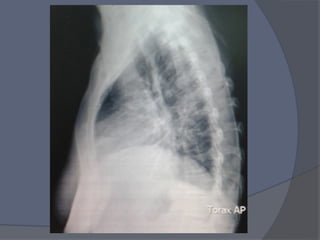

TAC AR

Aumento de

Grosor de

Pericardio

8mm

rodeando las 4

cavidades .

NO SG de

DERRAME

PERICARDICO

SIGNFICATIV

O

TAC AR Aumento de Grosorde Pericardio 8mm rodeando las 4 cavidades . NO SG de DERRAME PERICARDICO SIGNFICATIV O

Notas del editor

• #22 Aumento de Grosor de Pericardio , alcanza 8mm en zonas de mayor grosor , rodeando las 4 cavidades ; NO SG de DERRAME PERICARDICO SIGNFICATIVO 4 cavidades cardiacas bien Ao calibre normal, A pulmonar 30 mm diametro Adenopatias Para – Ao IZQUIERDAS la de mayor tamaño mas de 9 mm REDONDA 1 Bula Apical Resto de parenquima normal Atelectasia subsegmentaria ibsal Estructuras abdominales visibles normales Osteofitos en columna y Mineralizacion visible disminuida ( sugiere osteoporosis) , no Fracturas